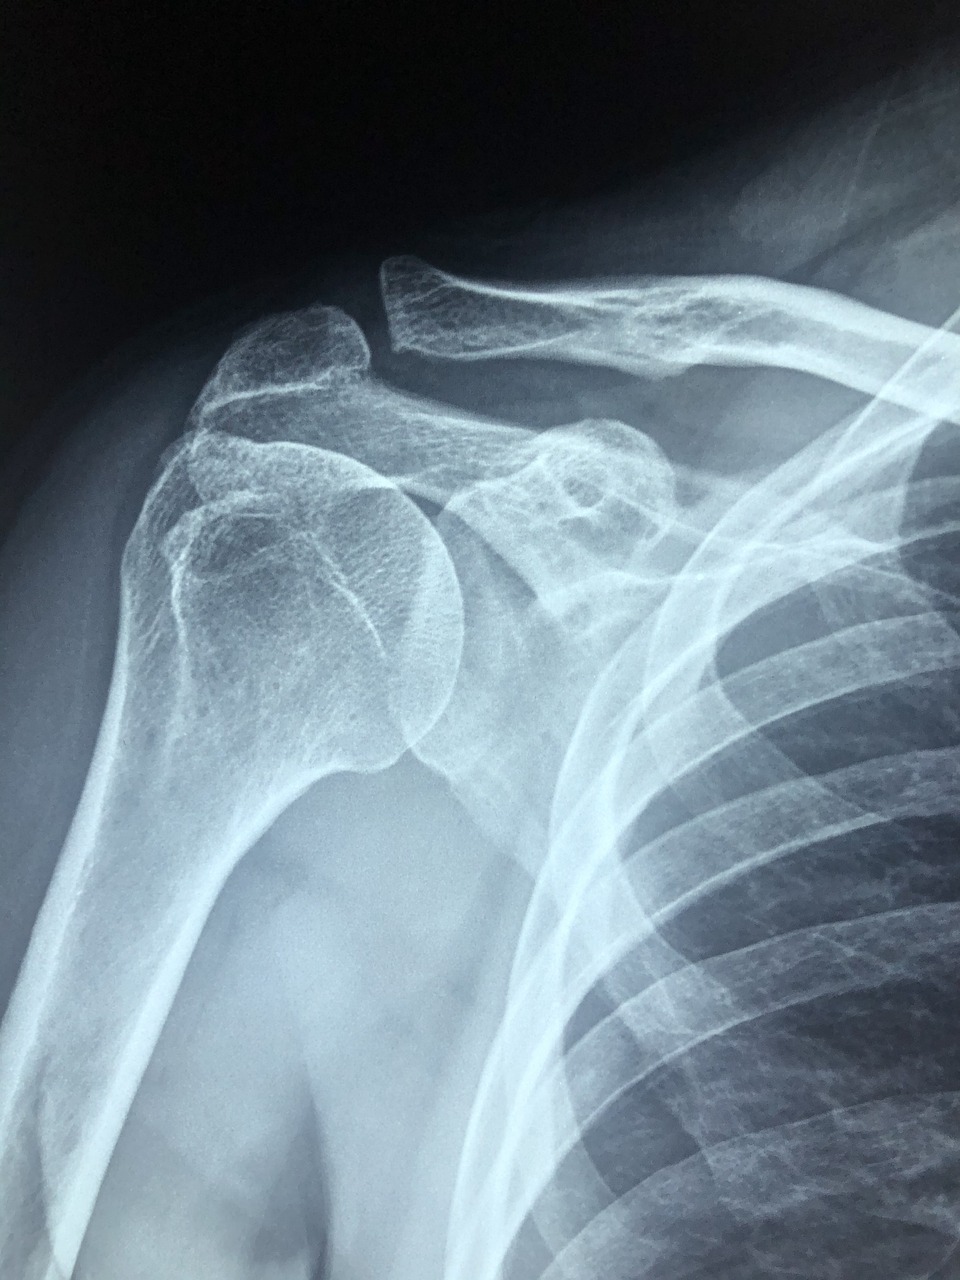

어깨충돌증후군은 어깨의 뼈와 힘줄이 서로 부딪히는 현상이라고 생각하시면 됩니다. 주로 팔을 위로 올릴 때 통증이나 불편함을 느끼게 되는데 이 증후군은 특히 컴퓨터 작업 등으로 팔을 많이 사용하는 현대 사회에서 흔히 발생하며 통증의 원인을 파악하는 것이 중요해요. 통증이 발생하는 이유를 이해하면 적절한 치료와 예방을 통해 일상생활에 미치는 불편함을 최소화할 수 있는 것이죠.

어깨충돌증후군의 증상은 다양하게 일어나지만 주로 팔을 움직일 때의 불편함 그리고 특정 자세에서의 통증이 주요 특징이에요. 조기 발견이 중요한 이유는 증상이 악화되면 치료가 더 어렵고 시간이 오래 걸릴 수 있기 때문입니다.

어깨충돌증후군을 조기에 발견하기 위해서는 전문가의 진단이 중요하지만 평소 자신의 건강 상태를 늘 확인하는 것이 도움이 됩니다. 어깨의 움직임이 제한되거나 통증이 느껴질 경우 정확한 진단을 통해 문제의 원인을 파악할 수 있는데요. 이를 통해 조기 치료가 가능해지며 장기적으로는 더 큰 부상으로 이어지는 것을 방지할 수 있어요.